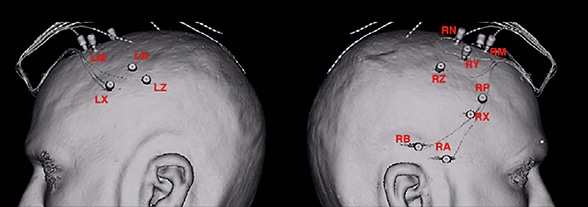

Positioning of electrodes for stereoelectroencephalography

Positioning of electrodes for stereoelectroencephalography

Illustrations indicate the positioning of electrodes for stereoelectroencephalography. On the left, positioning is indicated in the left anterior supplementary motor area (LM), left posterior supplementary motor area (LN), left anterior cingulate (LX) and left posterior cingulate (LZ). On the right, positioning is indicated in the right anterior temporal lobe (RA), right posterior temporal lobe (RB), right anterior supplementary motor area (RM), right posterior supplementary motor area (RN), right far anterior cingulate (RP), right anterior cingulate (RX), right middle cingulate (RY) and right posterior cingulate (RZ).